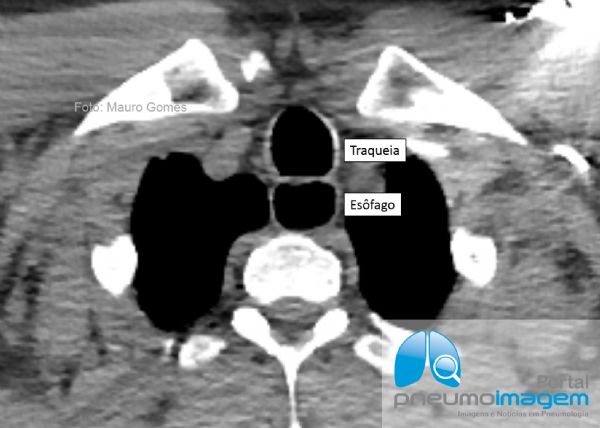

Nesse corte tomográfico se observa o diâmetro aumentado da luz do esôfago, que se encontra quase do mesmo tamanho da luz da traqueia, configurando megaesôfago. Esse paciente de 69 anos possui asma alérgica e eosinofílica há 20 anos e vem bem controlado apenas com o uso de corticoide inalatório (mometasona). Há cinco anos com mal-estar noturno e um episódio referido de pneumonia, quando foi suspeitada e confirmada Doença do Refluxo Gastroesofágico por impedancio-phmetria (RGE não ácido proximal patológico correlacionado com os sintomas).

In this CT slice, the increased diameter of the esophageal lumen is observed, which is almost the same size as the lumen of the trachea, configuring the megaesophagus. This 69-year-old patient has had allergic and eosinophilic asthma for 20 years and has been well controlled only with the use of inhaled corticosteroids (mometasone). Five years ago with nocturnal malaise and an episode of pneumonia, when gastroesophageal reflux disease (GERD) was suspected and confirmed by impedance-pH-metry (non-proximal GERD correlated with symptoms).